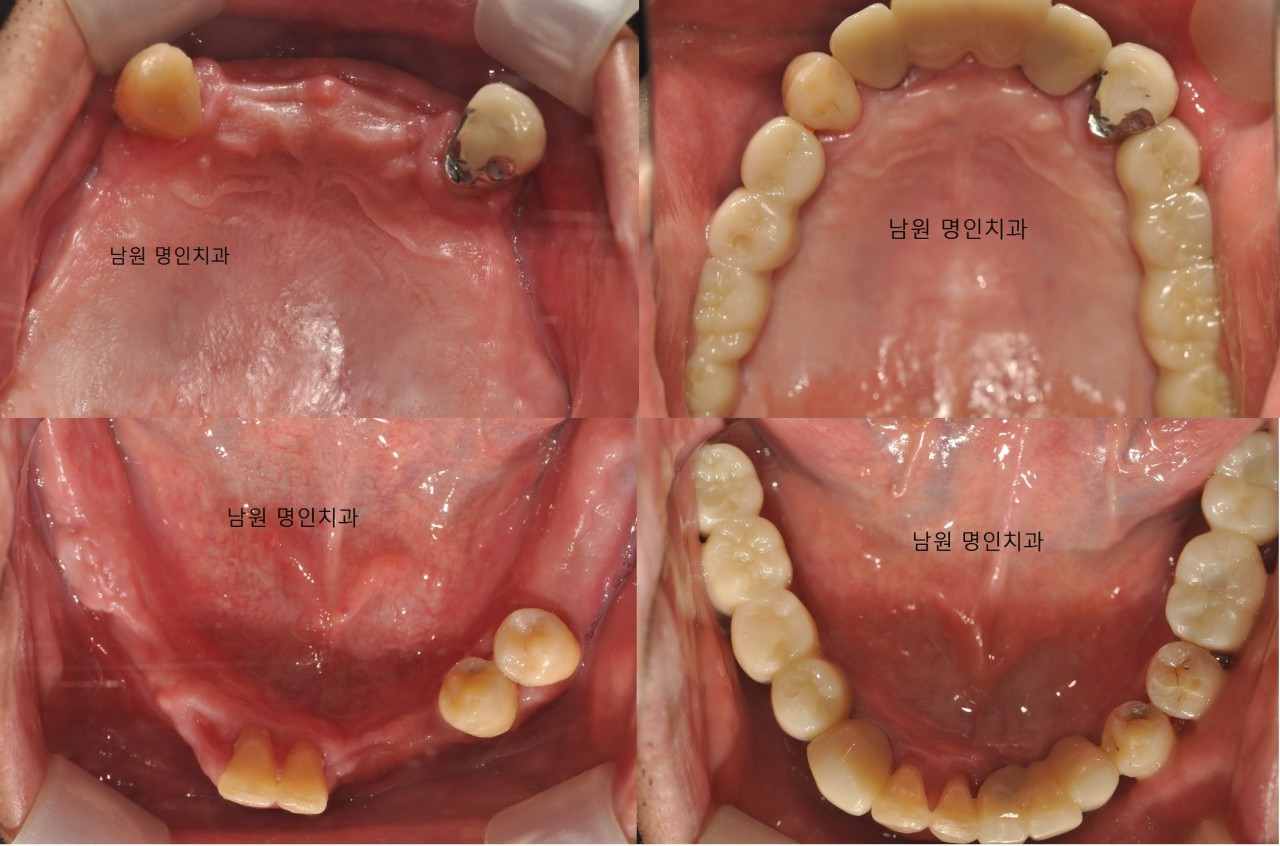

☞ 명인치과의원

- 주소 : 전북 남원시 용성로 98

- 연락처 : 063-626-2878

- 리뷰 : 방문자리뷰 144, 블로그리뷰 45